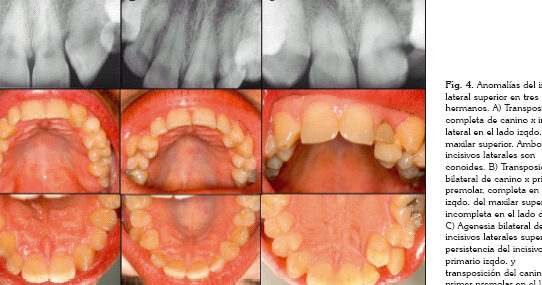

Anomalías de posición

Las anomalías de posición se refieren a dientes que están mal alineados o desplazados en la arcada dental. Esto puede incluir dientes apiñados, dientes impactados o dientes que erupcionan en una posición incorrecta. Estas anomalías pueden ser causadas por factores genéticos, falta de espacio en la boca o malos hábitos como chuparse el dedo. Las anomalías de posición pueden afectar la función masticatoria, la alineación de los dientes y la estética de la sonrisa, y pueden requerir tratamiento ortodóntico.